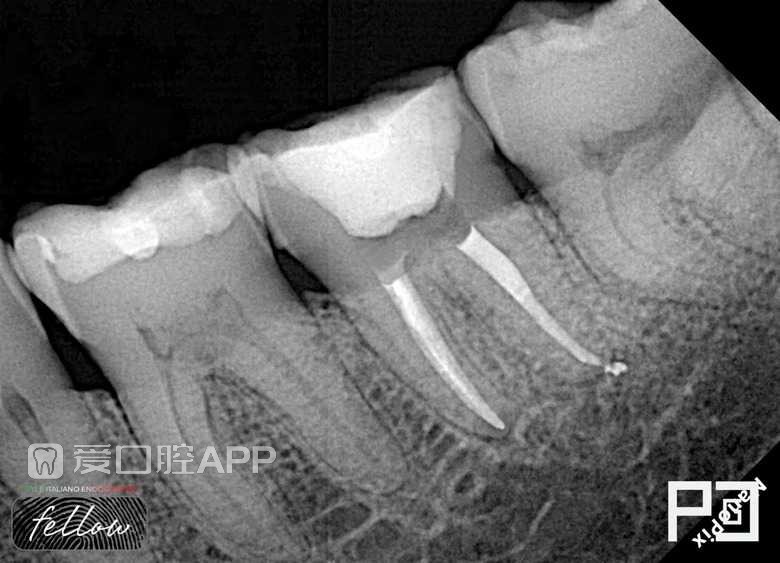

看个根充 —— 下7

by Paco CG